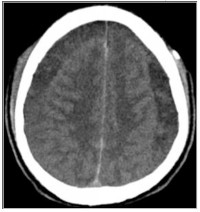

Background: Intracranial subdural haematomas (SDH) after subarachnoid blocks (SAB) are a very rare complication, which results in persistence of post procedure headaches and neurologic deterioration. Acute change in CSF pressure dynamics resulting in tears of bridging veins has been implicated.

Methods: Patients who had persistent headaches with neurologic deterioration after SAB had brain imaging done. Those with SDH were recruited. They had burr hole evacuation of haematomas.

Results: Twelve patients (11 females), with a mean age of 41.0±9.8 years were recruited. Ten patients had SAB, and 2 had Combined spinal epidural (CSE) anaesthesia. SAB was done with size 22G spinal needle in 3 patients and 24G in 5 patients. Confusion, headaches, alteration in consciousness, and paresis occurred in 66.7%, 100%, 75% and 83.3% of patients respectively. 16.7% patients were Mark-Walder grade IV, 8.3% grade III, 41.7% grade II, and 33.3% with grade I. 41.7% patients had bilateral SDH and 33.3% had left SDH. Chronic SDH was noted in 41.7% patients and others had subacute SDH. Mean interval between onset of symptoms to surgery was 6.3±7.3 days. Clinical recoveries were noted in all patients with postoperative modified Rankin Scale (mRS) scores at 14 days of 0.

Conclusion: Intracranial subdural haematomas may be rare but are a major cause of headaches with neurologic deteriorations after subarachnoid blocks. A high index of suspicion and prompt management results in good outcomes.